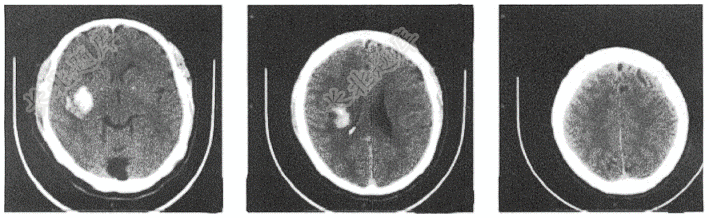

- 简答题患者女,51岁,突发语言障碍伴右侧肢体乏力3小时

- 女,62岁。体检头CT检查如图,最可能的

- 男性,55岁,头都摔伤3小时,头颅CT平